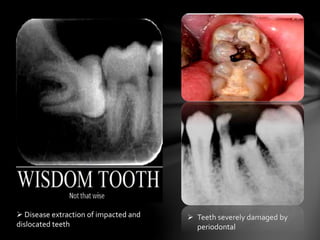

 Teeth severely damaged by

periodontal

 Disease extraction of impacted and

dislocated teeth